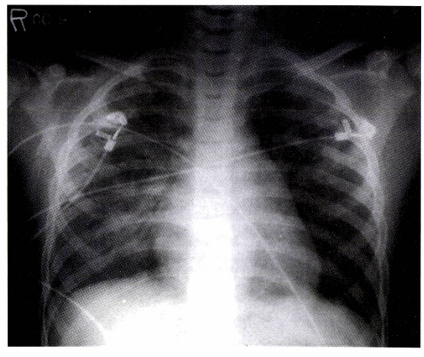

• 영상 검사: 흉부 X선

• 초기에는 정상일 수 있으며, 기관지 주변/혈관 주변 침윤이 우선적으로 나타남

• 후기: 나비 패턴 (양측 사이질/폐포 침윤)

• 심인성: 심비대

폐부종 흉부 X-ray: 전 폐야에 걸친 폐침윤 증가, 폐경결 (consolidation) 관찰